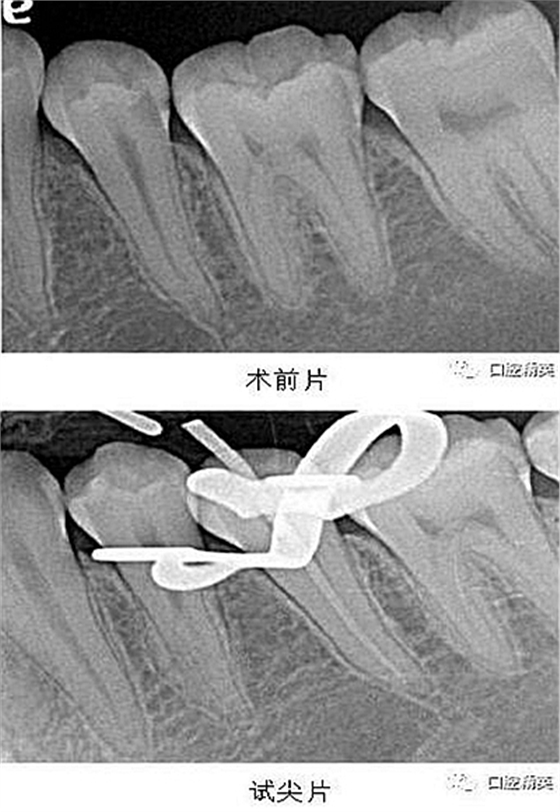

X-ray 可見(jiàn):35 遠(yuǎn)中齲壞累及髓腔,牙周膜增寬。

處置:經(jīng)患者及家屬知情同意后,35 局麻,放置橡皮障,去腐,開(kāi)髓,可見(jiàn)黑色感染物流出,定位根管口,建立直線通路,10# K 銼疏通根管,確定工作長(zhǎng)度(19mm),機(jī)用鎳鈦器械(M3),次氯酸鈉全程浸泡沖洗,預(yù)備根管至 35 號(hào),0.04 錐度,2ml EDTA 沖洗液緩慢勻速?zèng)_洗,超聲蕩洗。試主尖 X-ray 可見(jiàn)恰充,吸潮紙尖拭干根管,導(dǎo)AH-Plus 糊劑,連續(xù)波熱牙膠垂直加壓充填,術(shù)后 X-ray可見(jiàn)根管恰充,SDR 封閉根管口,復(fù)合樹(shù)脂充填窩洞,恢復(fù)牙齒形態(tài),調(diào)牙合,拋光。醫(yī)囑